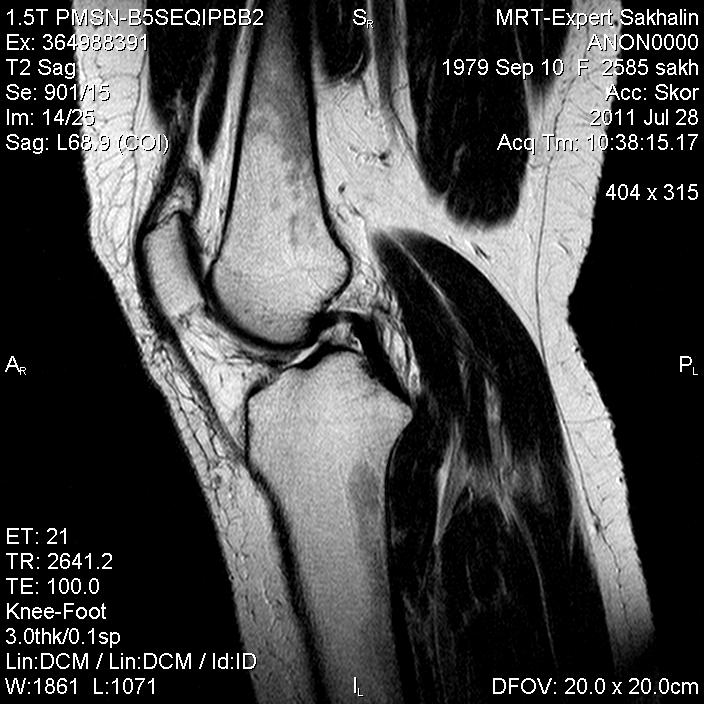

Коленный сустав

Подглядела случай у коллеги.

Что это может быть?

Не вижу криминала. А на что жалуется девушка?

P.S. В костях - это, скорее всего, резидуальный красный костный мозг.

Жалоба у всех одна на всех-болит.

участки гемопоэтического костного мозга